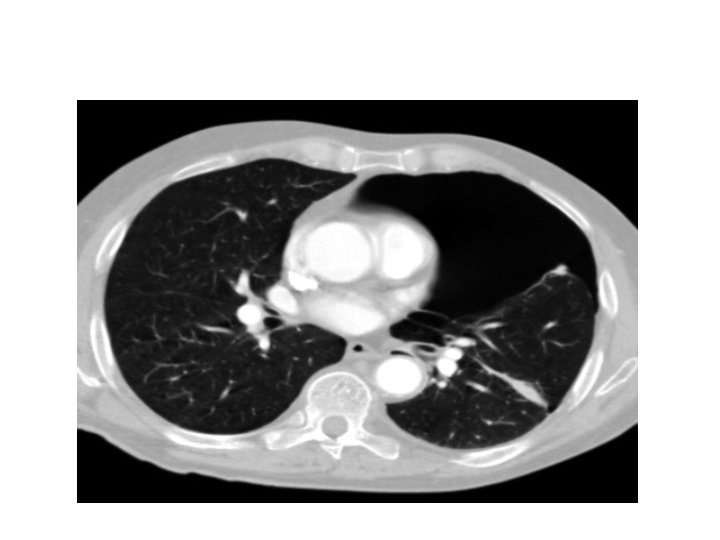

Pneumo thorax due to pulmonary laceration

Pulmonary contusion may mask pulmonary laceration on plain chest film. . Associated flail chest

Pulmonary contusion may mask pulmonary laceration on plain chest film. . Associated flail chest and sub cut. Emphysema